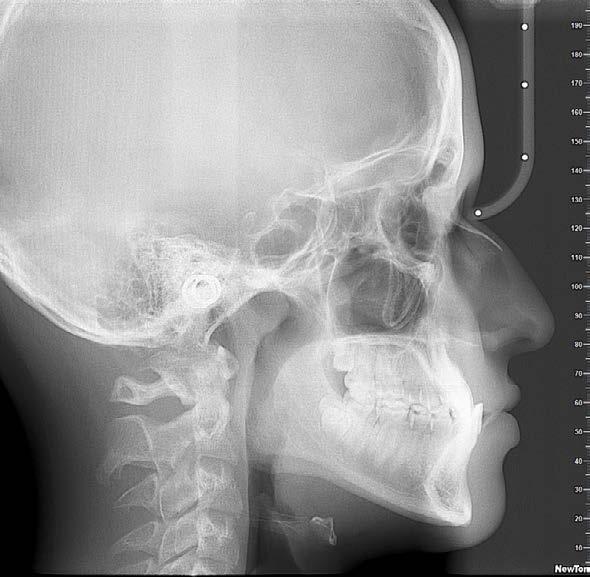

Figura 3. Radiografías iniciales.

A nivel radiográfico podemos observar densidad ósea uniforme, la presencia de 4 gérmenes dentarios correspondientes a los terceros molares y una relación corona-raíz 2:1. Se puede observar el patrón de crecimiento horizontal (Figura 3).

En la radiografía lateral de cráneo mediante la cefalometría de Steiner podemos observar que es un paciente con crecimiento horizontal ya que presenta un ángulo Go-Gn / SN de 28°, un ANB de -4°, podemos observar que el SNA está reducido, lo que nos da el efecto de un maxilar retraído (Figura 4).